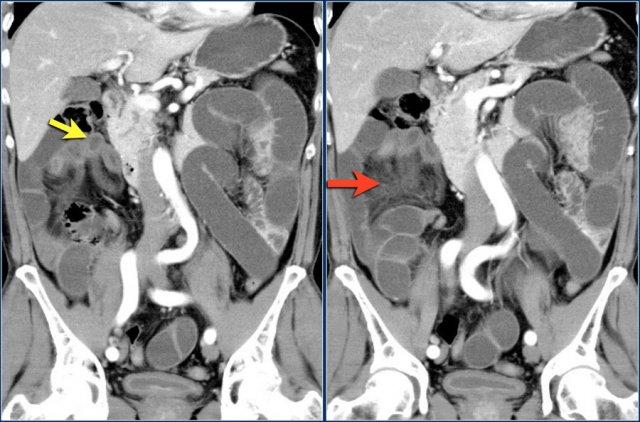

Các hình ảnh này thuộc về bệnh nhân bị tắc ruột non dạng quai kín.

Lưu ý nhóm các quai ruột non có thành dày ở vùng bụng trên phải (mũi tên vàng).

Phù nề mạc treo ruột (mũi tên đỏ) cho thấy tình trạng tăng áp lực tĩnh mạch do thắt nghẹt.

Giãn mạch máu

Tăng áp lực tĩnh mạch trong thắt nghẹt cũng dẫn đến giãn tĩnh mạch (mũi tên vàng).

Bệnh nhân này cũng có tắc ruột dạng quai kín với kiểu ngấm thuốc xám của các quai ruột bị thắt nghẹt (mũi tên đỏ).

Lưu ý sự ngấm thuốc bình thường của ruột non ở phía trên vị trí tắc nghẽn (mũi tên xanh lá).

Một bệnh nhân khác với hình ảnh ruột thiếu máu cục bộ và phù nề mạc treo ruột lan rộng.

Trong phẫu thuật, toàn bộ đoạn ruột non này đã bị hoại tử.